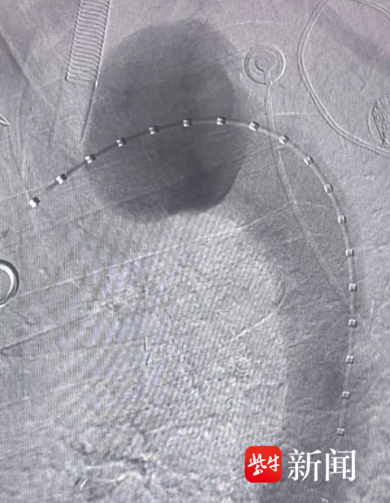

该手术属于微创介入治疗,具有创伤小、治疗效果明显、恢复快、并发症少等优点,更适合宋爷爷这样的高龄高危患者。术中,麻醉科团队全程护航,确保患者生命体征平稳。喻四龙主任带领介入科团队在DSA引导下,行胸主动脉造影,清晰地“描绘”出动脉瘤的形态、大小和位置。随后,小心翼翼地将一枚主动脉支架精准释放,将脆弱的瘤体与高速血流隔离开来,消除了瘤体破裂、出血的隐患。紧接着,又通过导管向动脉瘤腔内填入弹簧圈,像“水泥”一样,进一步促进瘤内血栓形成,加固“防线”,彻底阻断动脉瘤的血流。2小时后,当“危险炸弹”被成功拆除的消息传来,所有人都松了一口气。

术前造影(左)、术后造影(右)